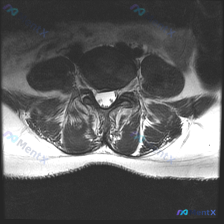

今天看到一个很有启发的读片病例,临床怀疑椎间盘病变,整理一下完整分析思路分享给大家。 病例影像信息 本次提供的是单张腰椎MRI T2序列轴位图像,分析观察结果如下: 1. 解剖结构:显示腰椎中下段某节段横断面,椎体、椎管硬膜囊、侧隐窝、椎间盘、后方椎板/黄韧带/关节突结构均清晰可辨 2. 椎间盘评估...

大家好,分享一个很有代表性的临床读片病例,整理了完整的分析思路,一起讨论。 病例基本信息 用户临床怀疑存在椎间盘病变,提供单张腰椎MRI T2序列轴位影像,要求分析评估。 --- 影像读片结果 这是下腰椎(L4/5或L5/S1水平)的轴位影像,读片发现: 1. 椎间盘:髓核信号正常,未见后缘突出压迫...

整理了一份腰椎MRI读片讨论,给大家分享一下思路。 病例影像基础信息 本次仅提供放射影像-腰椎MRI-T2序列-轴位单张图像,扫描层面为腰椎某一节段,视觉判断符合腰4/5或腰5/骶1椎间盘水平,无临床病史、体征及其他检查资料,核心问题是明确该层面是否存在椎间盘病变相关影像学表现。 影像具体读片结果...

今天整理了一份只有单张腰椎MRI T2加权轴位片的椎间盘病变分析案例,跟大家分享一下读片和临床分析的思路。 病例影像基本信息 本次仅提供单张腰椎MRI T2加权轴位图像,具体读片发现如下: 1. 节段定位:根据椎体、椎弓根和关节突形态判断,该切面位于腰椎,最可能为L4/5或L5/S1水平 2. 椎间...